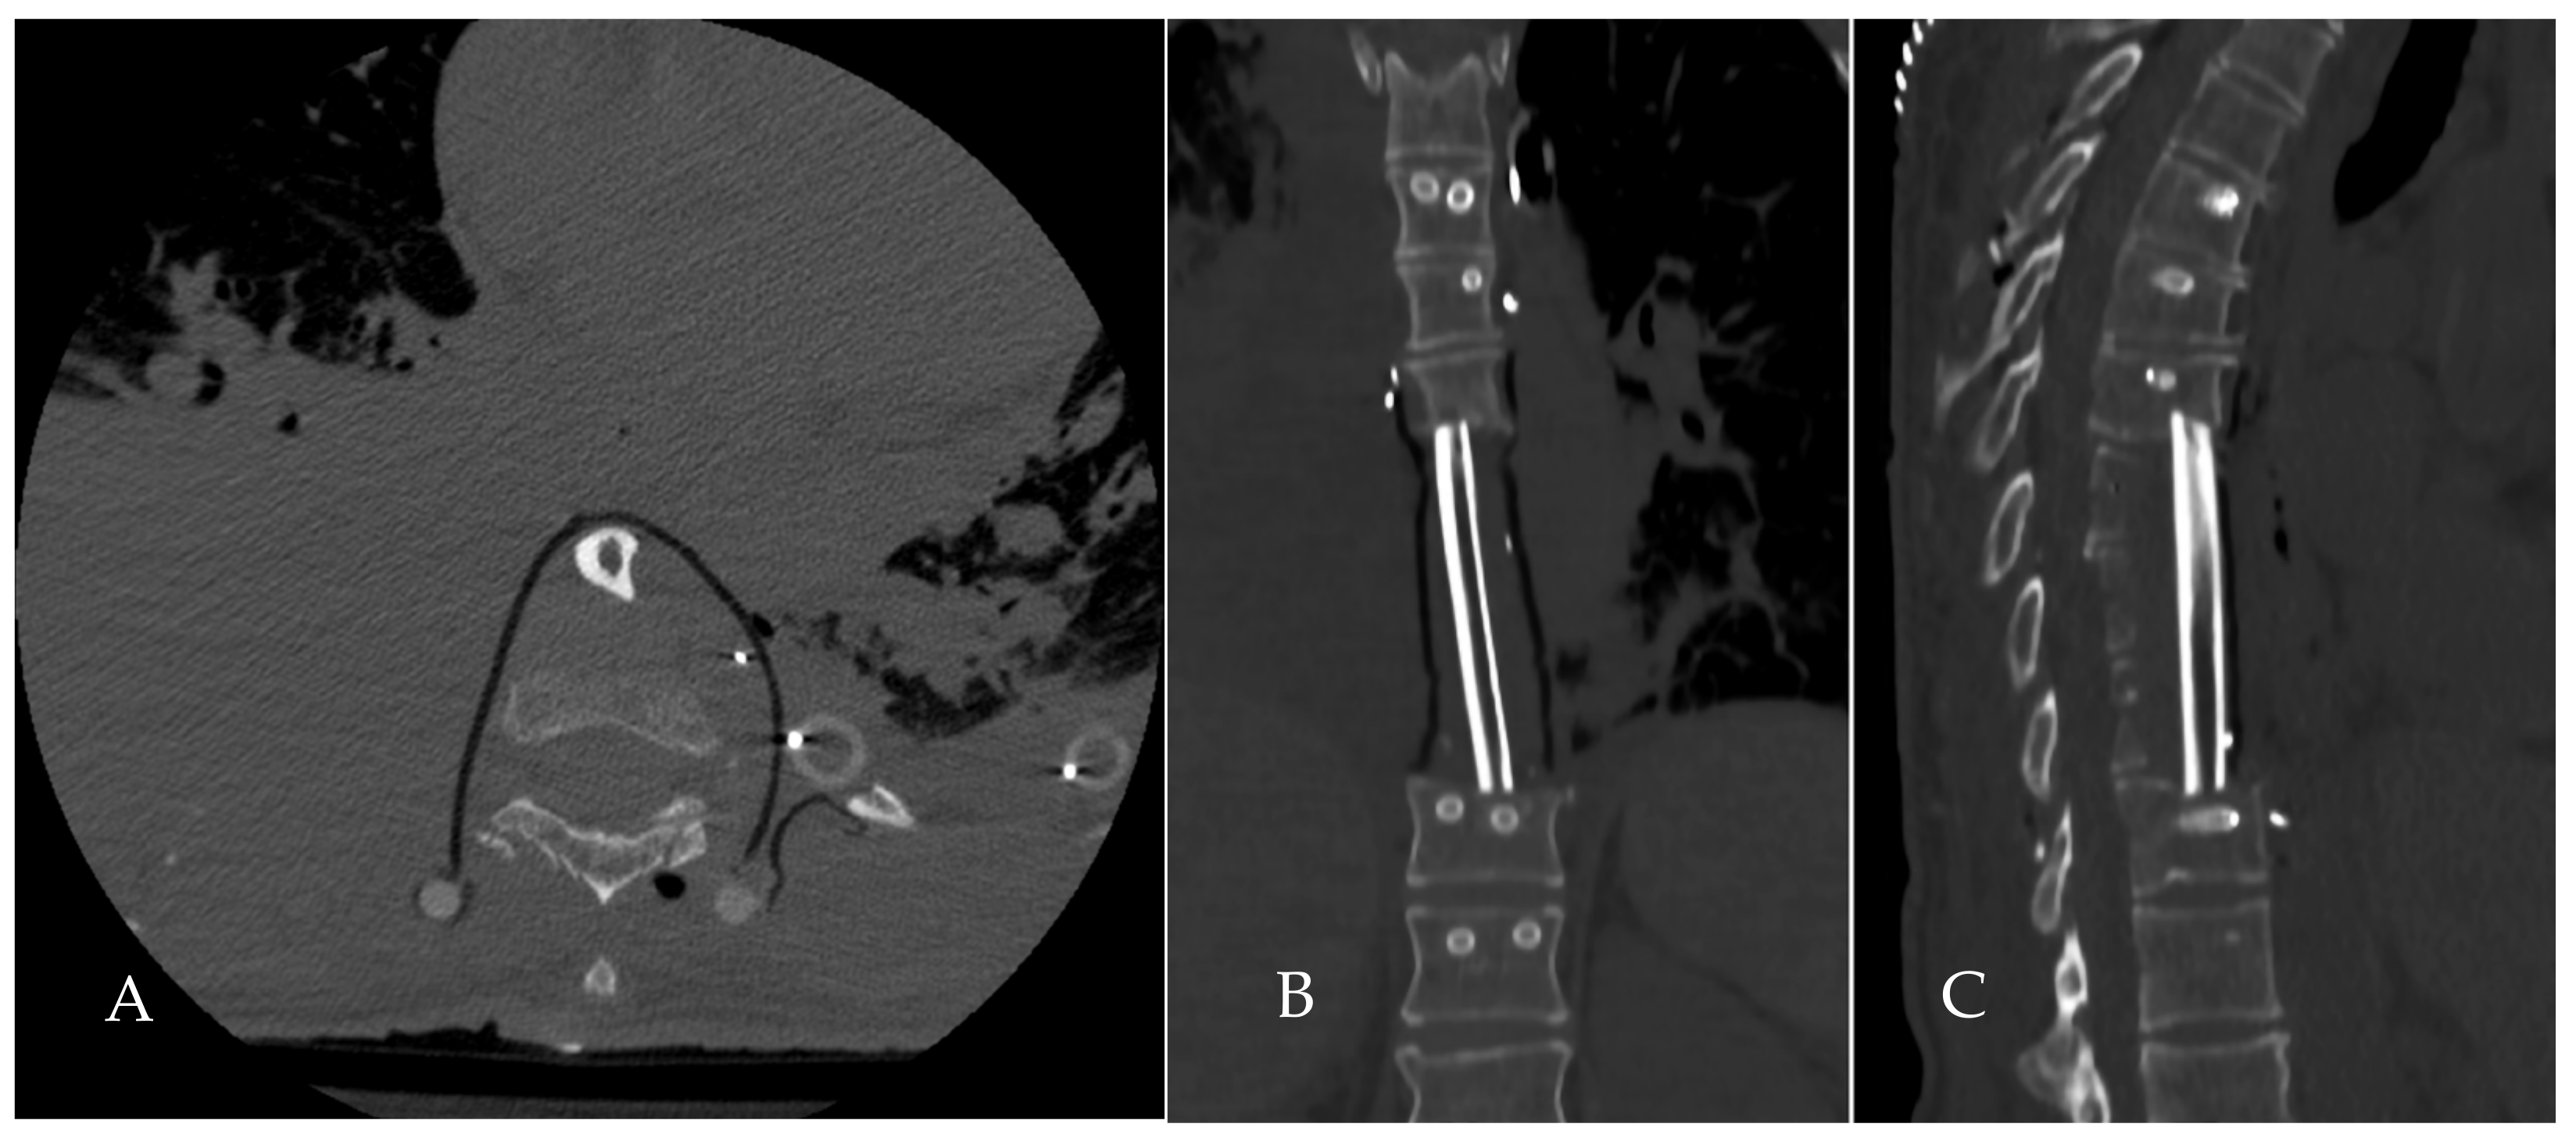

2.3. Surgical Planning

2.4. Surgical Procedure

2.5. Reconstruction